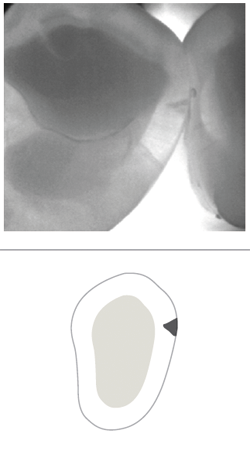

• No involvement, sound tooth structure (Fig. 6)

• At the first detectable signs of an enamel caries lesion (Fig. 7)

• An established caries lesion (Fig. 8)

• An established caries lesion that has reached the DEJ at a single point (Fig. 9)